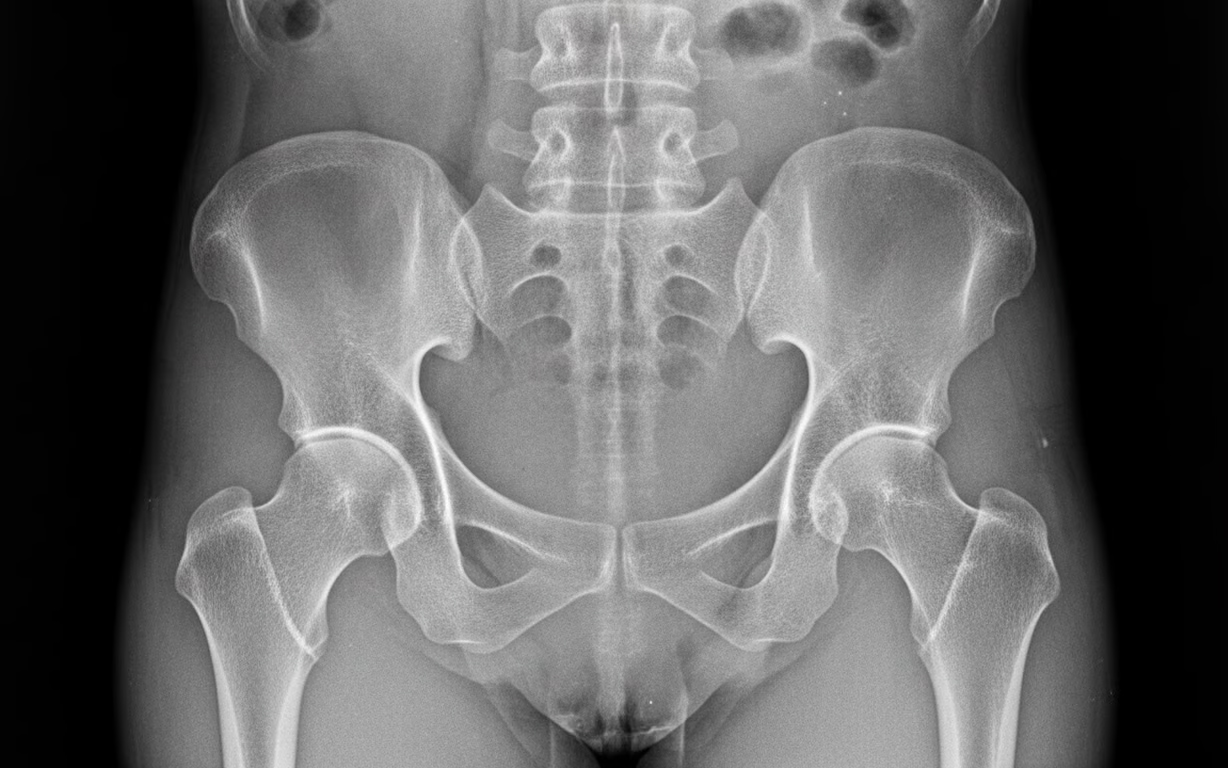

· Radiografii osoase, care pot evidenția:

· demineralizare osoasă difuză;

· subțierea cortexului osos;

· fracturi sau zone Looser (fracturi incomplete), caracteristice osteomalaciei.